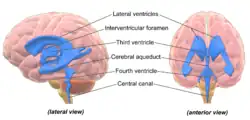

Aging entails many physical, biological, chemical, and psychological changes and the brain is no exception to this phenomenon. These various changes have attempted to be mapped by conceptual models like the Scaffolding Theory of Aging and Cognition (STAC) in 2009. The STAC model looks at factors like neural changes to the white matter, dopamine depletion, shrinkage, and cortical thinning.[5] CT scans have found that the cerebral ventricles expand as a function of age. More recent MRI studies have reported age-related regional decreases in cerebral volume.[6][7] Regional volume reduction is not uniform; some brain regions shrink at a rate of up to 1% per year, whereas others remain relatively stable until the end of the life-span.[8] The brain is very complex, and is composed of many different areas and types of tissue, or matter. The different functions of different tissues in the brain may be more or less susceptible to age-induced changes.[6] The brain matter can be broadly classified as either grey matter, or white matter. Grey matter consists of cell bodies in the cortex and subcortical nuclei. White matter consists of tightly packed myelinated axons connecting the neurons to each other and with the periphery.[6]

Cerebral blood flow was shown to decrease 0.3-0.5% per year in healthy ageing.[31] An efficiently functioning glymphatic system, involved in waste clearance, may be important for maintaining brain health and its transport efficiency appears to be declining with aging.[32] Factors in the circulation have been shown to modulate ageing and to rejuvenate the brain.[33]